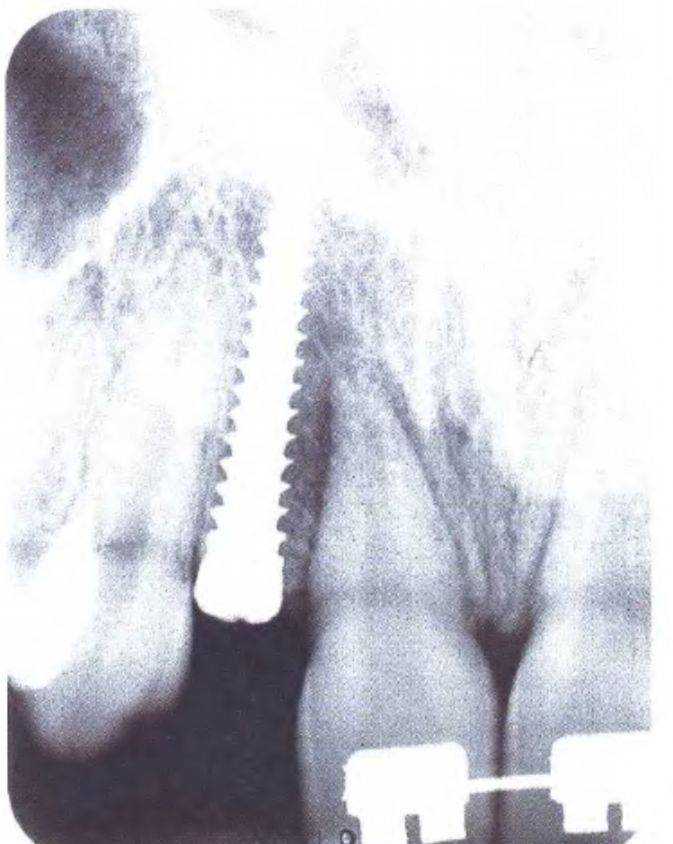

На первом этапе устранили диастему между верхними центральными резцами, чтобы создать пространство в области боковых резцов для установки имплантатов, что выполнили с помощью ортодонтического лечения (рис. с 3-39f по 3-39i). Прицельные рентгенограммы показали достаточное увеличение пространства (рис. 3-39j и 3-39к). Расстояние между верхушками корней можно было увеличить еще больше при использовании ретракционной проволочной дуги с петлями. Следует обсудить с ортодонтом варианты ортодонтического лечения. При проведении рентгенологической диагностики не следует соблюдать рекомендованный производителем оборудования протокол - необходимо подобрать параметры, которые используются при параллельном расположении зуба относительно пленки. Это позволяет полностью отобразить протрузионную и ретрузионную плоскости одновременно. Сотрудники стоматологической клиники, проводящие рентгенологическую диагностику, должны владеть этой методикой.

Рис. 3-39j (слева). Рентгенограмма для оценки пространства в области отсутствующего правого бокового резца

Рис. 3-39к (справа). Рентгенограмма для оценки пространства в области отсутствующего левого бокового резца